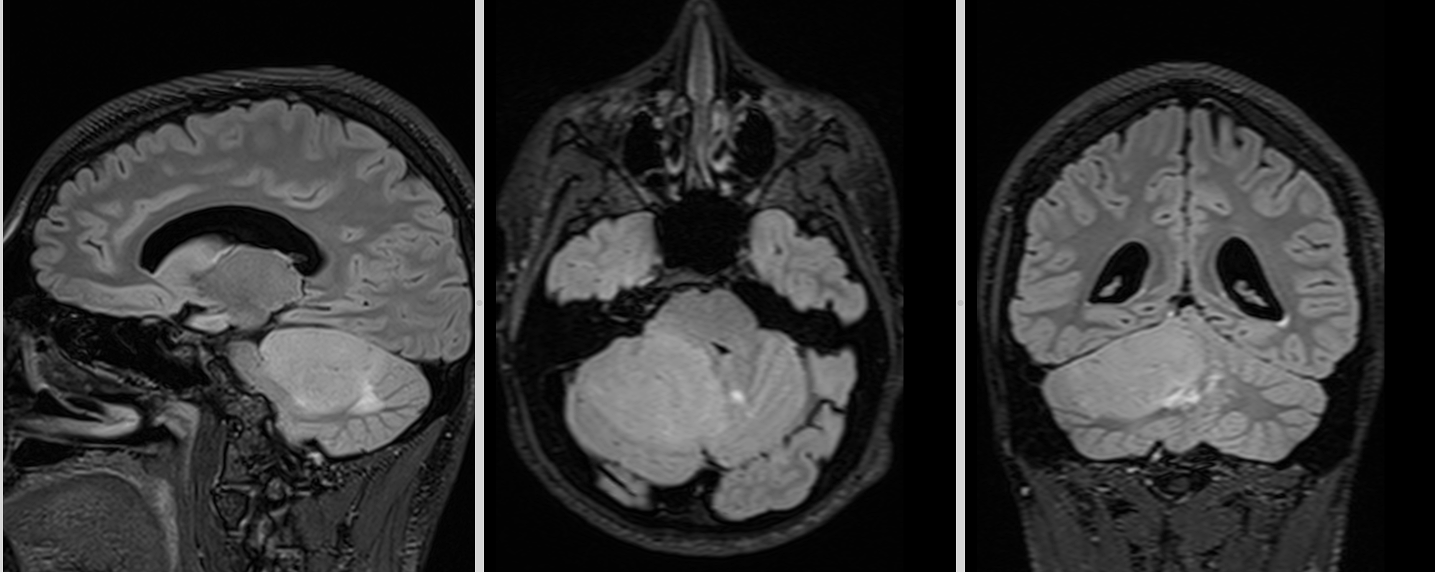

RMN cerebral

Este investigația de elecție. Meduloblastomul apare de obicei ca:

- leziune solidă, bine delimitată sau infiltrativă

- hipointensă T1, hiperintensă T2

- captare intensă de contrast

- posibilă restricție de difuzie (densitate celulară mare)

La adult, localizarea în emisfera cerebeloasă poate duce la confuzie cu alte tumori (metastaze, hemangioblastom, astrocitom).